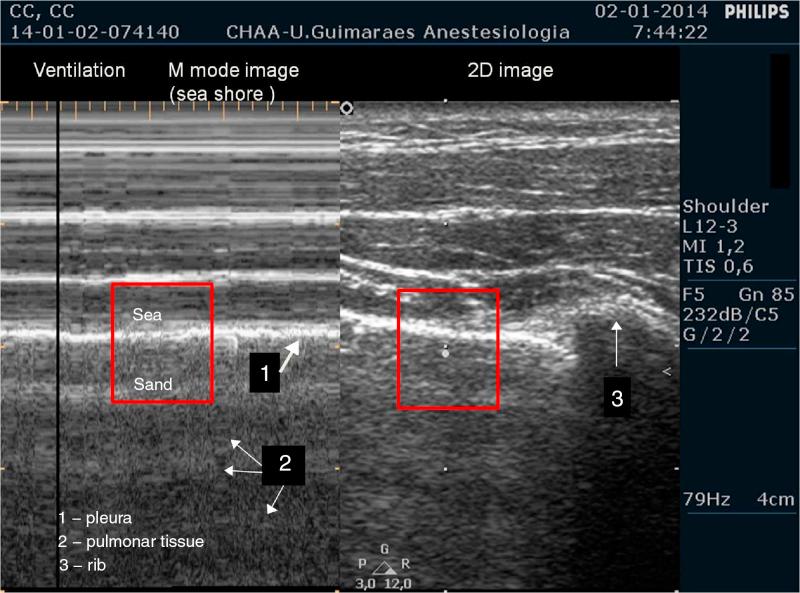

Ultrasound has increasingly growing applications in anesthesia. This procedure has proven to be a novel, non-invasive and simple technique for the upper airway management, proving to be a useful tool, not only in the operating room but also in the intensive care unit and emergency department. Indeed, over the years mounting evidence has showed an increasing role of ultrasound in airway management. In this review, the authors will discuss the importance of ultrasound in the airway preoperative assessment as a way of detecting signs of difficult intubation or to define the type and/or size of the endotracheal tube as well as to help airway procedures such as endotracheal intubation, cricothyrotomy, percutaneous tracheal intubation, retrograde intubation as well as the criteria for extubation.

超声在麻醉领域的应用日益广泛。该技术已被证明是一种用于上气道管理的新颖、无创且简便的技术,不仅在手术室,而且在重症监护病房和急诊科都是一种有用的工具。事实上,多年来越来越多的证据表明超声在气道管理中的作用日益增强。在本综述中,作者将讨论超声在气道术前评估中的重要性,它可用于检测困难插管的迹象、确定气管内导管的类型和/或尺寸,以及辅助诸如气管内插管、环甲膜切开术、经皮气管插管、逆行插管等气道操作,还有拔管标准。